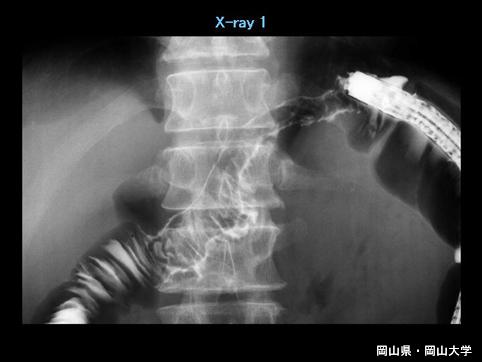

症例提示(所在地,施設名等): 岡山県・ 岡山大学附属病院 (Dr.那須)

疾患(病理主体)の分類炎症性・潰瘍性疾患/アメーバ赤痢

部位(臓器別)大腸/横行

検査方法X-P

病変の最大径(ミリ)40以上